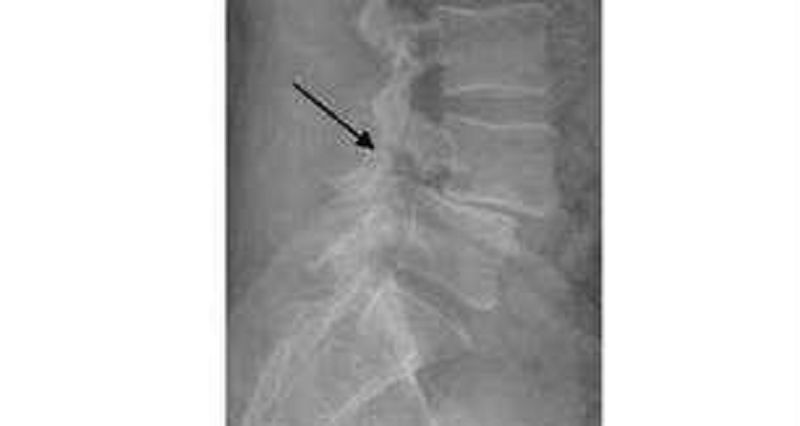

Welche 2 Zeichen in Bezug auf Röntgenbilder sind wichtig bei einer Spondylolisthese?

Umgekehrte Napoleonshut

Hündchen mit Halsband